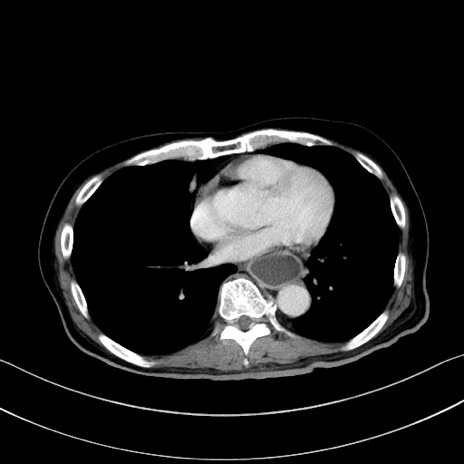

冠状断像

【症例】60歳代男性

【主訴】嘔吐

【現病歴】胃癌にて胃全摘後。食思不振が悪化し、夜中に嘔吐することがある。

【既往歴】胃癌、胃全摘、脾摘、胆摘後

【データ】WBC 5900、CRP 10.56